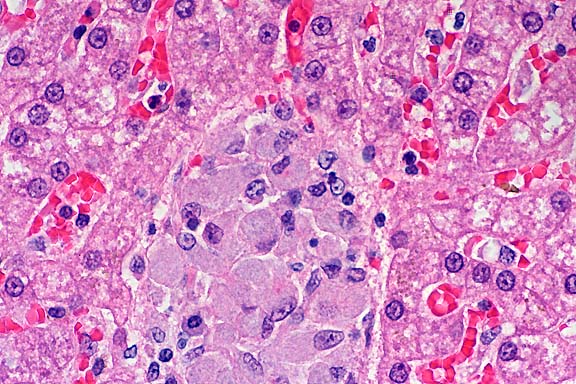

20x

obj.

- Case 3-3. Spleenic artery. Within the splenic arteries

there are abundant large 20-30u cells with granular cytoplasm,

open faced nuclei and a single prominant nuclei (interpreted

as macrophages containing protozoal organisms). Similar macrophages

are scattered around the artery in the red pulp.